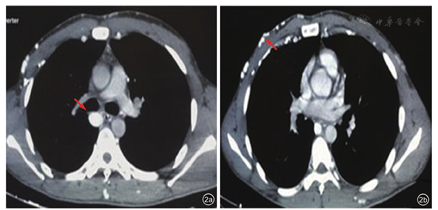

肝脏超声未见异常。胸部增强CT检查提示:右侧锁骨下静脉,上腔静脉均未显示,考虑闭塞。胸壁静脉扩张强化明显,右侧奇静脉扩张代偿。前纵膈高密度影,胸腺退化不全可能性大(图2a,图2b)。

颈内静脉超声检查(2016-12-10):双侧颈内静脉(图3a, 图3b, 图3c)、双侧头臂静脉血栓形成(完全型,图3d, 图3e, 图3f)。双侧锁骨下静脉血栓(图4a, 图4b, 图4c);腹壁浅静脉逆流经大隐静脉至股总静脉下腔静脉回心,胸腹壁迂曲静脉扩张(反流,图4d, 图4e, 图4f)。